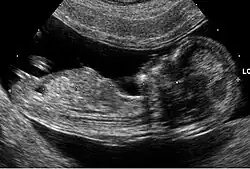

Les anomalies échographiques sont également prises en compte. Il s'agit de la recherche de malformations classiques de la trisomie 21 (comme les malformations cardiaques) et aussi de «marqueurs dont le plus important est l'épaisseur de la clarté nucale. D'autres signes sont discutés car difficiles à mesurer avec des résultats variables selon les observateurs. Toutefois, à la fin des années 2000, la combinaison entre la mesure de la clarté nucale et l'âge maternel est considérée comme un marqueur puissant d'une probabilité de trisomie 21[40].